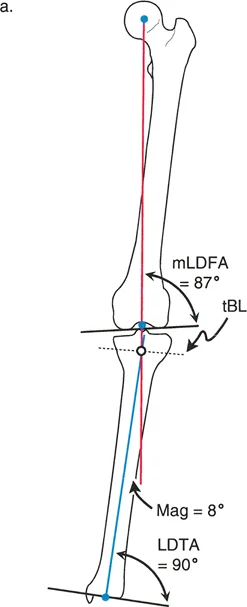

- أشعة الساق الكاملة الواقفة (Full-length Standing X-rays): هذه هي الأداة التشخيصية الأكثر أهمية لتشوهات الأطراف. يتم أخذ الصورة بينما يقف المريض، مما يسمح بتقييم المحور الميكانيكي للطرف بأكمله (من الورك إلى الكاحل) تحت تأثير تحمل الوزن. تتيح هذه الصور للجراح قياس زوايا محددة بدقة وتحديد "مركز دوران التشوه" (CORA) – وهو النقطة المحورية التي يجب أن يتم التصحيح حولها.

إن نجاح جراحة تصحيح تشوهات الأطراف يعتمد بشكل كبير على التخطيط المسبق الدقيق. هذا التخطيط أشبه برسم خارطة طريق هندسية تضمن أن كل خطوة جراحية تقود إلى النتيجة المرجوة. يعتمد هذا التخطيط على "مبادئ بالي" التي تحدد ثلاثة متغيرات هندسية أساسية في كل حالة:

- مركز دوران التشوه (CORA - Center of Rotation of Angulation): هذه هي النقطة المحورية للتشوه في العظم. يحددها الجراح من خلال رسم محاور الطرف قبل الجراحة.

- محور تصحيح الزاوية (ACA - Angulation Correction Axis): هذه هي النقطة التي يدور حولها الجزء البعيد من العظم لتصحيح التشوه. يتحكم الجراح في هذه النقطة عن طريق وضع المفصلات على المثبت الخارجي أو نقطة الارتكاز للوحة التثبيت.

- مستوى قطع العظم (Osteotomy Level): هذا هو الموقع الفعلي الذي يتم فيه قطع العظم. يتحكم الجراح بشكل كامل في هذا المتغير، ويتم اختياره بناءً على عوامل مثل الأنسجة الرخوة، وجودة العظم، ونوع الأجهزة المستخدمة.

النتيجة النهائية للتصحيح تعتمد كليًا على كيفية ارتباط هذه المتغيرات الثلاثة ببعضها البعض. الفشل في التخطيط الدقيق يمكن أن يؤدي إلى "تشوهات ثانوية" غير مرغوب فيها، مثل انحراف المحور الميكانيكي أو ترجمة (إزاحة) العظم.